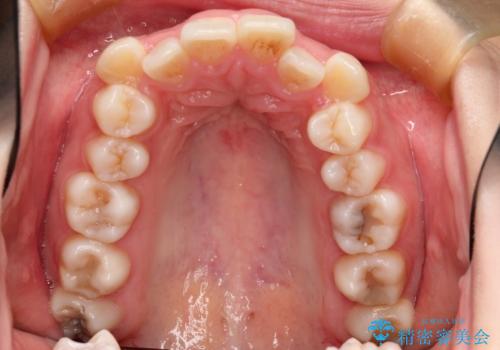

- 前歯のデコボコと上顎の前突感による口の閉じにくさを気にして来院された患者様です。

目立たない装置を希望されたので、上顎が裏側装置のハーフリンガルを選択し、上下左右の小臼歯(計4歯)を抜歯して矯正治療を行うこととしました。